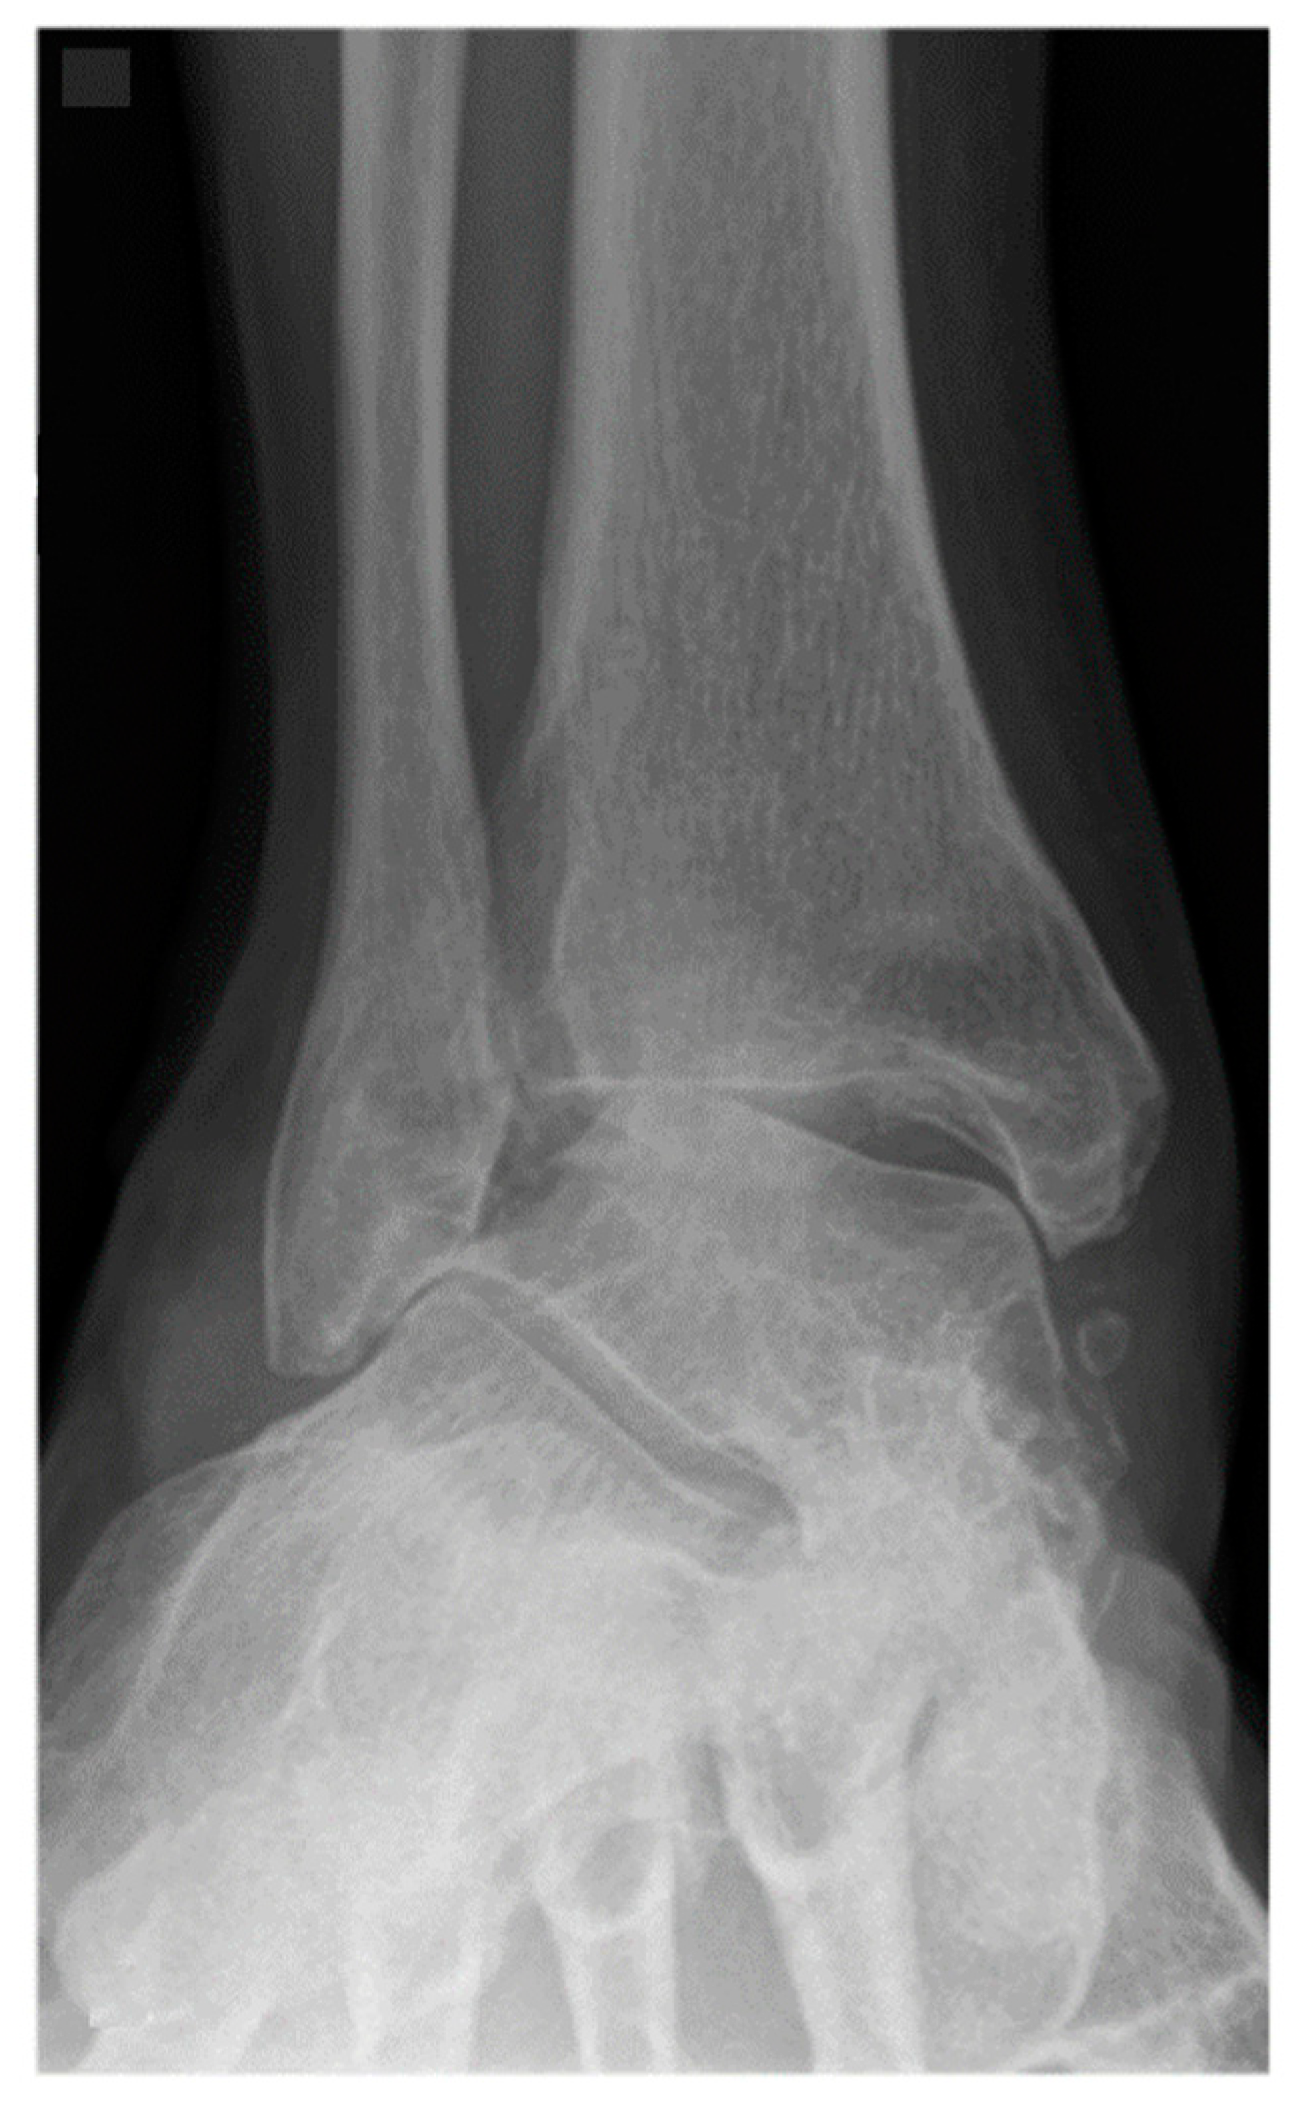

Figure 2.

A 62-year-old female patient presenting end-stage valgus tibiotalar osteoarthritis.

Operative approach, fixation method, choice of allograft/autograft/bone graft substitutes were varied based on surgeon and patient factors. Figure 2 shows radiographs of a typical case in this study in which the distal tibiofibular arthrodesis was included in the construct. In each case the foot was positioned in slight valgus, external rotation, and dorsiflexion and provisionally fixated for fluoroscopic imaging. If the foot position was deemed satisfactory, the tibiotalar joint +/− distal tibiofibular joint were fixated. Final fluoroscopic images were routinely obtained prior to closing the wounds and placing post-operative immobilization with use of a splint or boot. There was not a standardized post-operative protocol, but all patients were instructed to be non-weight bearing for a minimum of 6 weeks after surgery. Generally, patients were followed at 2, 6, and 12 weeks, 6 month, and 1-year intervals.